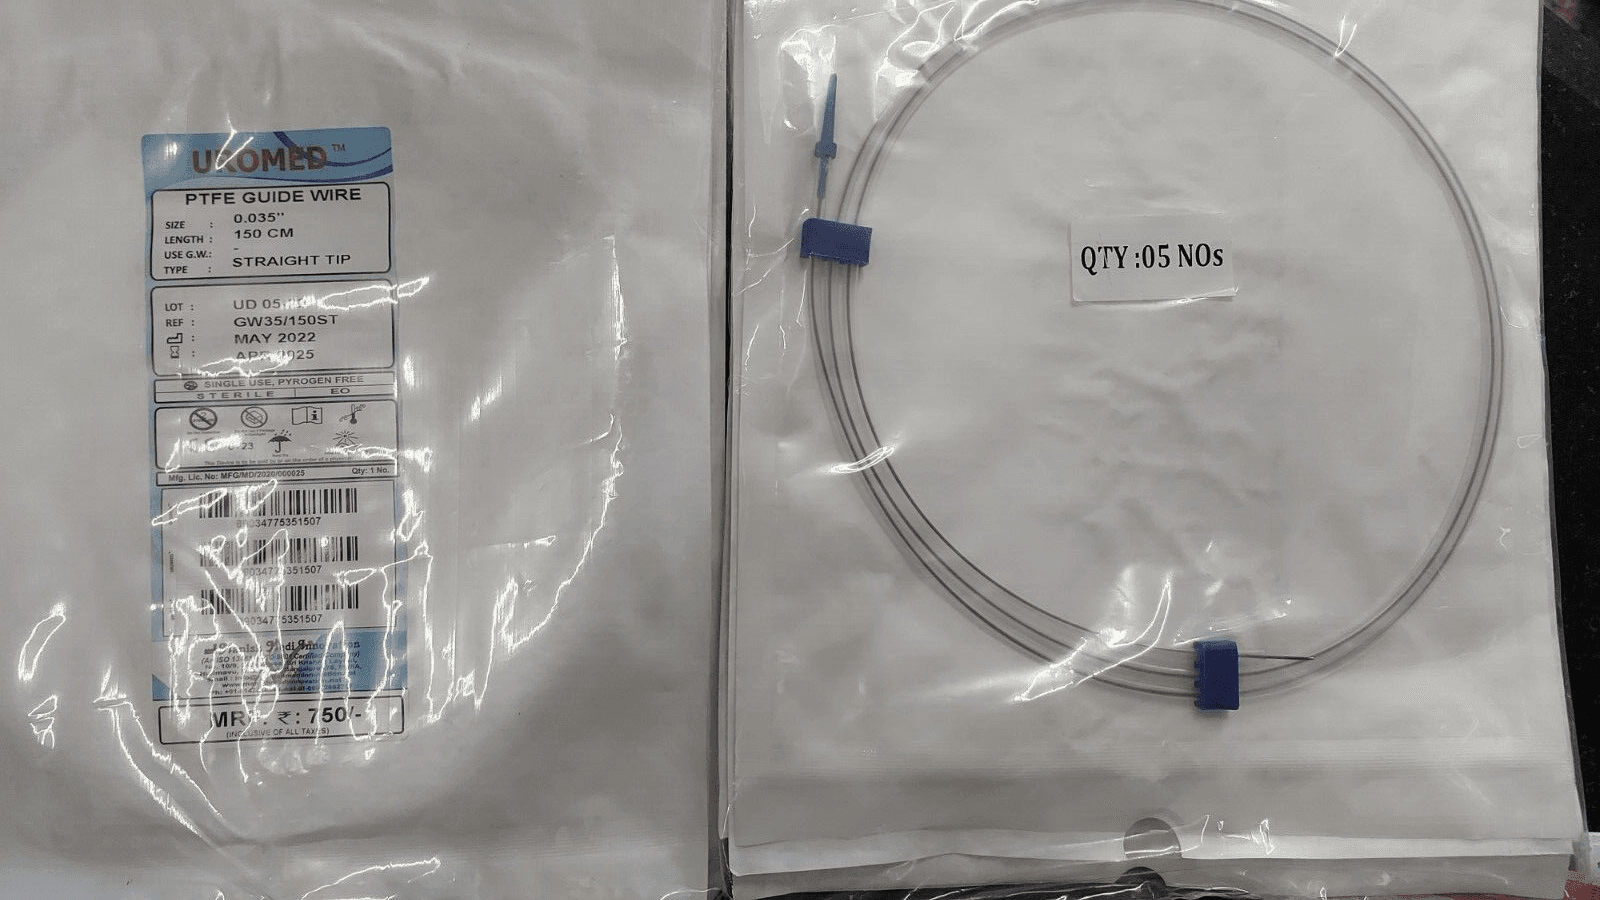

PTFE Guide Wire Set of 10 Urology Size 0.035 Length 150cm Straight

PTFE Guide Wire Set of 10 Urology Size 0.035 Length 150cm Straight

Guide wire with and without PTFE coating

- This wire is made by Galvanized Stainless Steel, and having fixed core. UROMED guide wire has excellent flexibility.

- Better push ability for increased placement control.

- Low of coefficient of friction for smooth advancement.

- Size: 0.035”

- Lengths: 150cm

Images are for illustration only. Company may change item design and packaging from time to time. We will ship latest stock available.